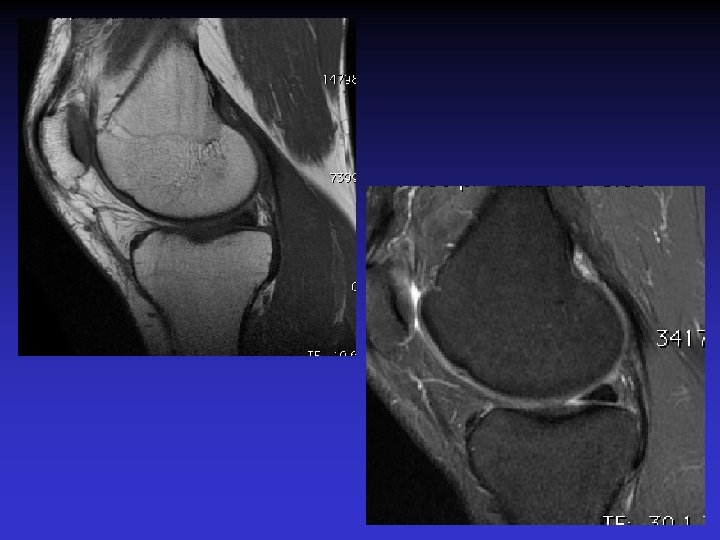

• Homme de 46 ans • Douleurs et sensation de blocage du genou • Pas de traumatisme récent mais « entorse ancienne » • Recherche de lésion méniscale

• • • Pas d’épanchement Pas de lésion méniscale Pas de lésion cartilagineuse Pas de lésion osseuse Anomalies du LCA • Épaissi • Hyper signal T 1 et T 2 • Orientation des fibres conservée • Kyste

ASPECT IRM • • Hyposignal TI Hypersignal T 2 Pas de prise du contraste après Gado IV Continuité conservée du LCA+++ avec dilacération des fibres • Aspect en « tige de céleri »